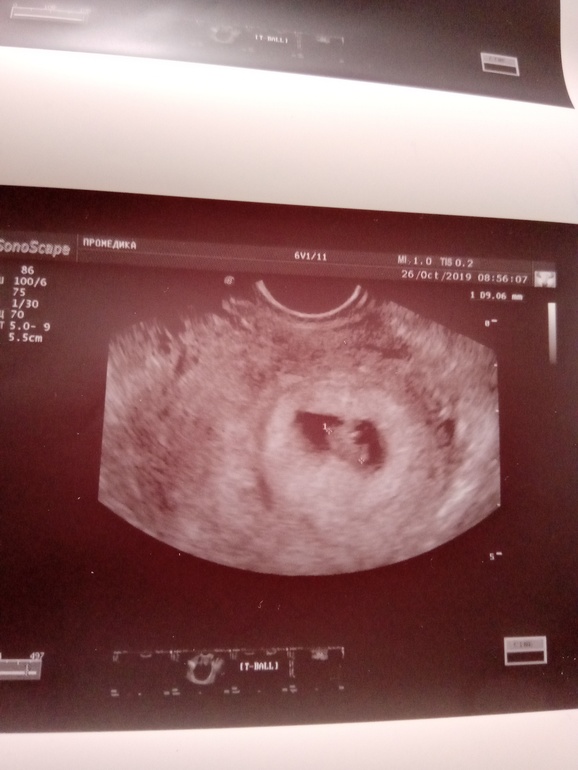

Третья беременностьУ меня внутри уже сантиметровый человечек)))) Невероятное что-то. Я никогда раньше не задумывалась, какой стремительный путь проходит маленький эмбрион. Ровно 2 недели назад на УЗИ ПЯ было 5,3 мм. А сегодня ПЯ

уже 2,4 см, а сам малепусик 9 мм. Соответствуем сроку 7 недель. ЧСС 150 уд/мин, желточный мешочек 4 мм, ЖТ 22 мм. Хорион по передней стенке, почти в дне. Шейка 37 мм.

Найти эмбрион сначала не могли. У меня аж все упало, когда я увидела круглое чёрное плодное яйцо без эмбриончика. Как-то он расположен интересно. С характером, говорит врач)))) датчик изворачивали кое-как, чтоб посмотреть.

Сердцебиние когда включили, я слезу пустила, конечно)))) Муж сиял, как начищенный самовар, сидя в углу кабинета и глядя на монитор. 😍 Кстати, Новосибирск, рекомендую клинику Про-медика на Кубовой. Очень приятная атмосфера, все рассказывают, показывают, на вопросы отвечают. Я была у Шишкиной Альбины Юрьевны. За УЗИ отдала всего 1000 руб. Белая полосочка у эмбриона справа - это ручка))))